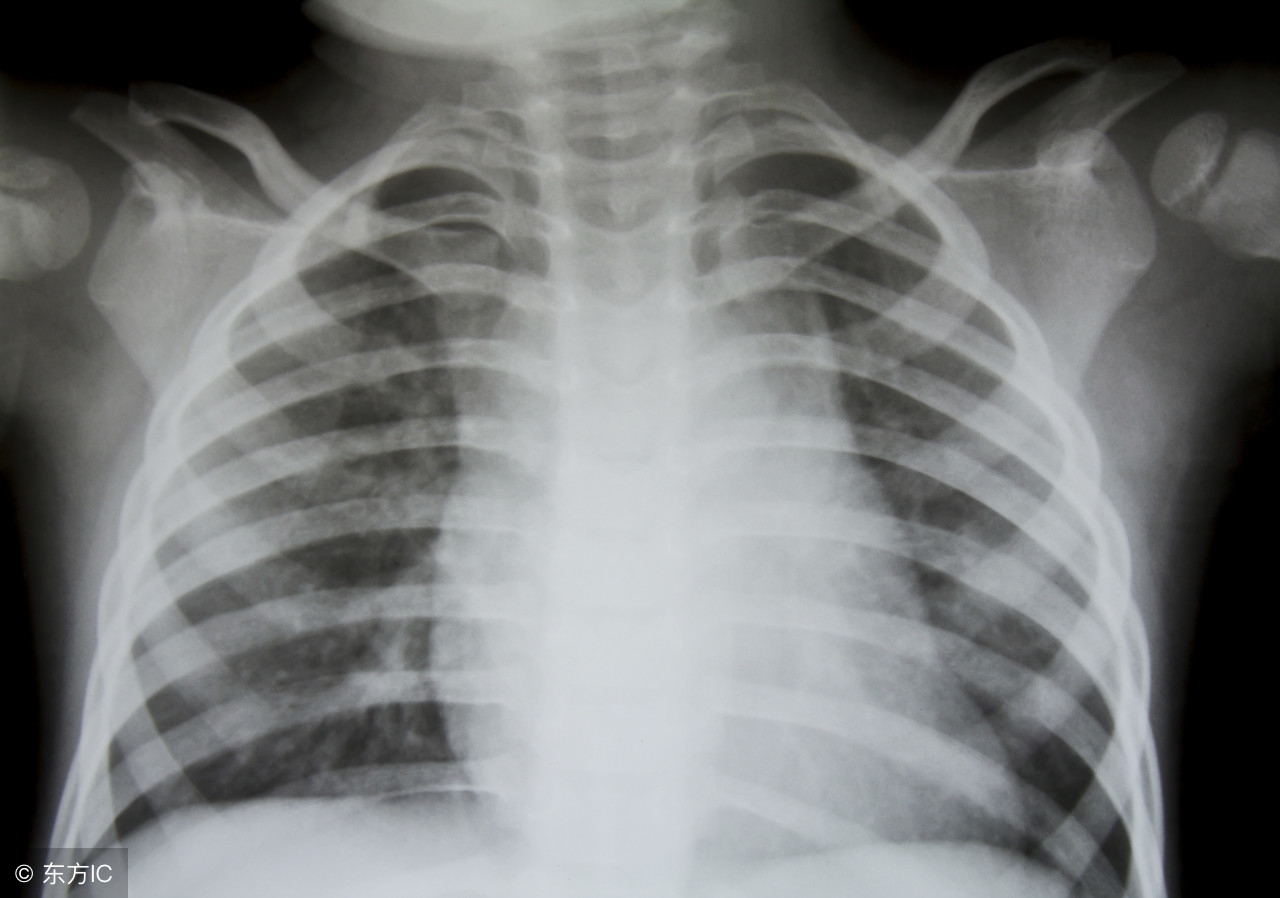

支气管炎会引起发烧的,建议还是CT或者胸片检查和化验血常规看看.如果确诊支气管炎或者呼吸道感染引起的,可以遵医嘱服用消炎药和止咳祛痰药物对症治疗,如服用头孢克罗胶囊和复方甘草口服溶液等,一般不能盲目服用药物,使用抗生素需要医生指导下服用.发热超过38.5时再服用退热药.避免引起药物副作用或者细菌耐药性.注意休息和多喝白开水.避免辛辣刺激性饮食。